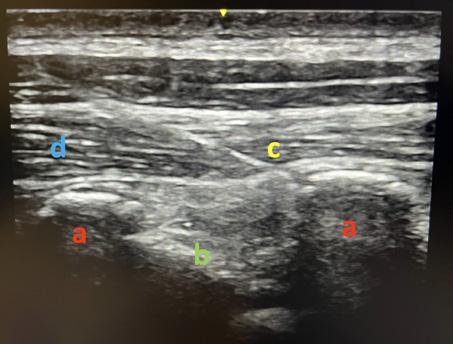

Table des illustrations

1. Korte, Wolfgang: Moderne Gerinnungsdiagnostik: wie hilft sie uns? http://www.anaesthesie-stgallen.ch/ Informationen_fuer_Fachpersonen/Fruehere_Veranstaltungen/IPS_Symposium_2008/05Korte.pdf

2. Görlinger K, Bergmann L & Dirkmann D. Coagulation management in patients undergoing mechanical circulatory support. Best Pract & Res Clin Anaesthesiol. 2012;26:179-198.

3. et 4. Gauger MS, Kaufmann P, Kamber F et al. Rotational Thromboelastometry Values After On-Pump Cardiac Surgery – A Retrospective Cohort Study. Semin Cardiothorac Vasc Anesth. 2022;26:209-220.

Laufbahnplanung auf

Die ideale Plattform für Berufs- und Bildungsprofile von Gesundheitsfachpersonen, weil

•alle Diplome und Zeugnisse an einem Ort zentral und elektronisch abgelegt sind

•ein stets aktueller Lebenslauf generiert werden kann